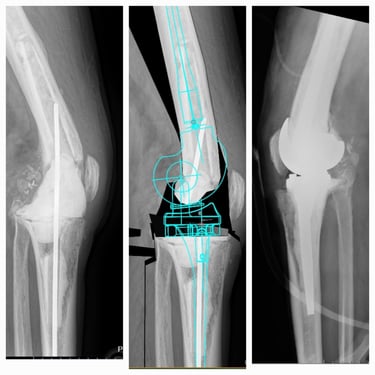

Artroplastia de rodilla (prótesis total/parcial).

Cirugía robótica de cadera y rodilla (en casos seleccionados).